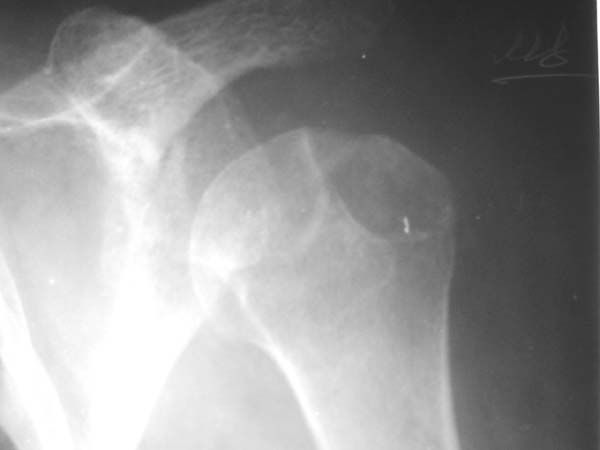

Уважаемые коллеги!Женщина, 60 лет. 3 недели назад упала с упором на отведенную левую руку. Почувствовала боль в левом плечевом суставе. За помощью не обращалась. 2 недели "мази и припарки". Затем - рентгенограмма (r1 и r2), жалобы на боли,ограничение движений...

Активное отведение 80 гр., при пальпации - головка плечевой кости безболезненно вправляется и тут же самостоятельно вывихивается. Наложена косыночная иммобилизация, рентгенография (r3) и МРТ.В нашем диагностическом центре МРТ исследование плечевого сустава выполнено впервые, опыта у нас маловато :(.Вопросы: уточнение диагноза? какие исследования провести? тактика лечения?

"Прицельная" съемка малопонятного очага.

1. На рентгене - нижний подвывих плеча и очаг остеолиза суставного бугорка с четкими контурами (вдавленный перелом на фоне остеопороза ? доброкачественная опухоль? аваскулярный некроз ? (хотя ни разу не слышал об аваскулярном некрозе плеча..)

Судя по снимкам, речь идTт о типичном случае Hill-Sachs Lesion. По этому поводу я позволю себе некоторый экскурс:

97 % всех вывихов плеча происходит по механизму комбинации отведения, разгибания и наружной ротации (А. Гринспан). В момент вывиха головка плеча ударяет о нижний край гленоида, что ведет к вдавленному или компрессионному перелому одной или обеих структур. Чаще всего, однако, повреждение возникает в задней латеральной области головки плечевой кости на переходе от головки к шейке. Этот диагноз можно выставить на основании рентгеновского снимка в переднезадней проекции с внутренней ротацией плеча. Несколько реже видно повреждение гленоида о передненижний перелом края. То, что мы называем Bankart Lesion. Это повреждение видно на ре. снимке в п.з. проекции при нейтральной позиции плеча. Разумеется хрящевые и мягкотканные повреждения (в смысле Банкарт) мы увидим лучше всего на ЯМР.